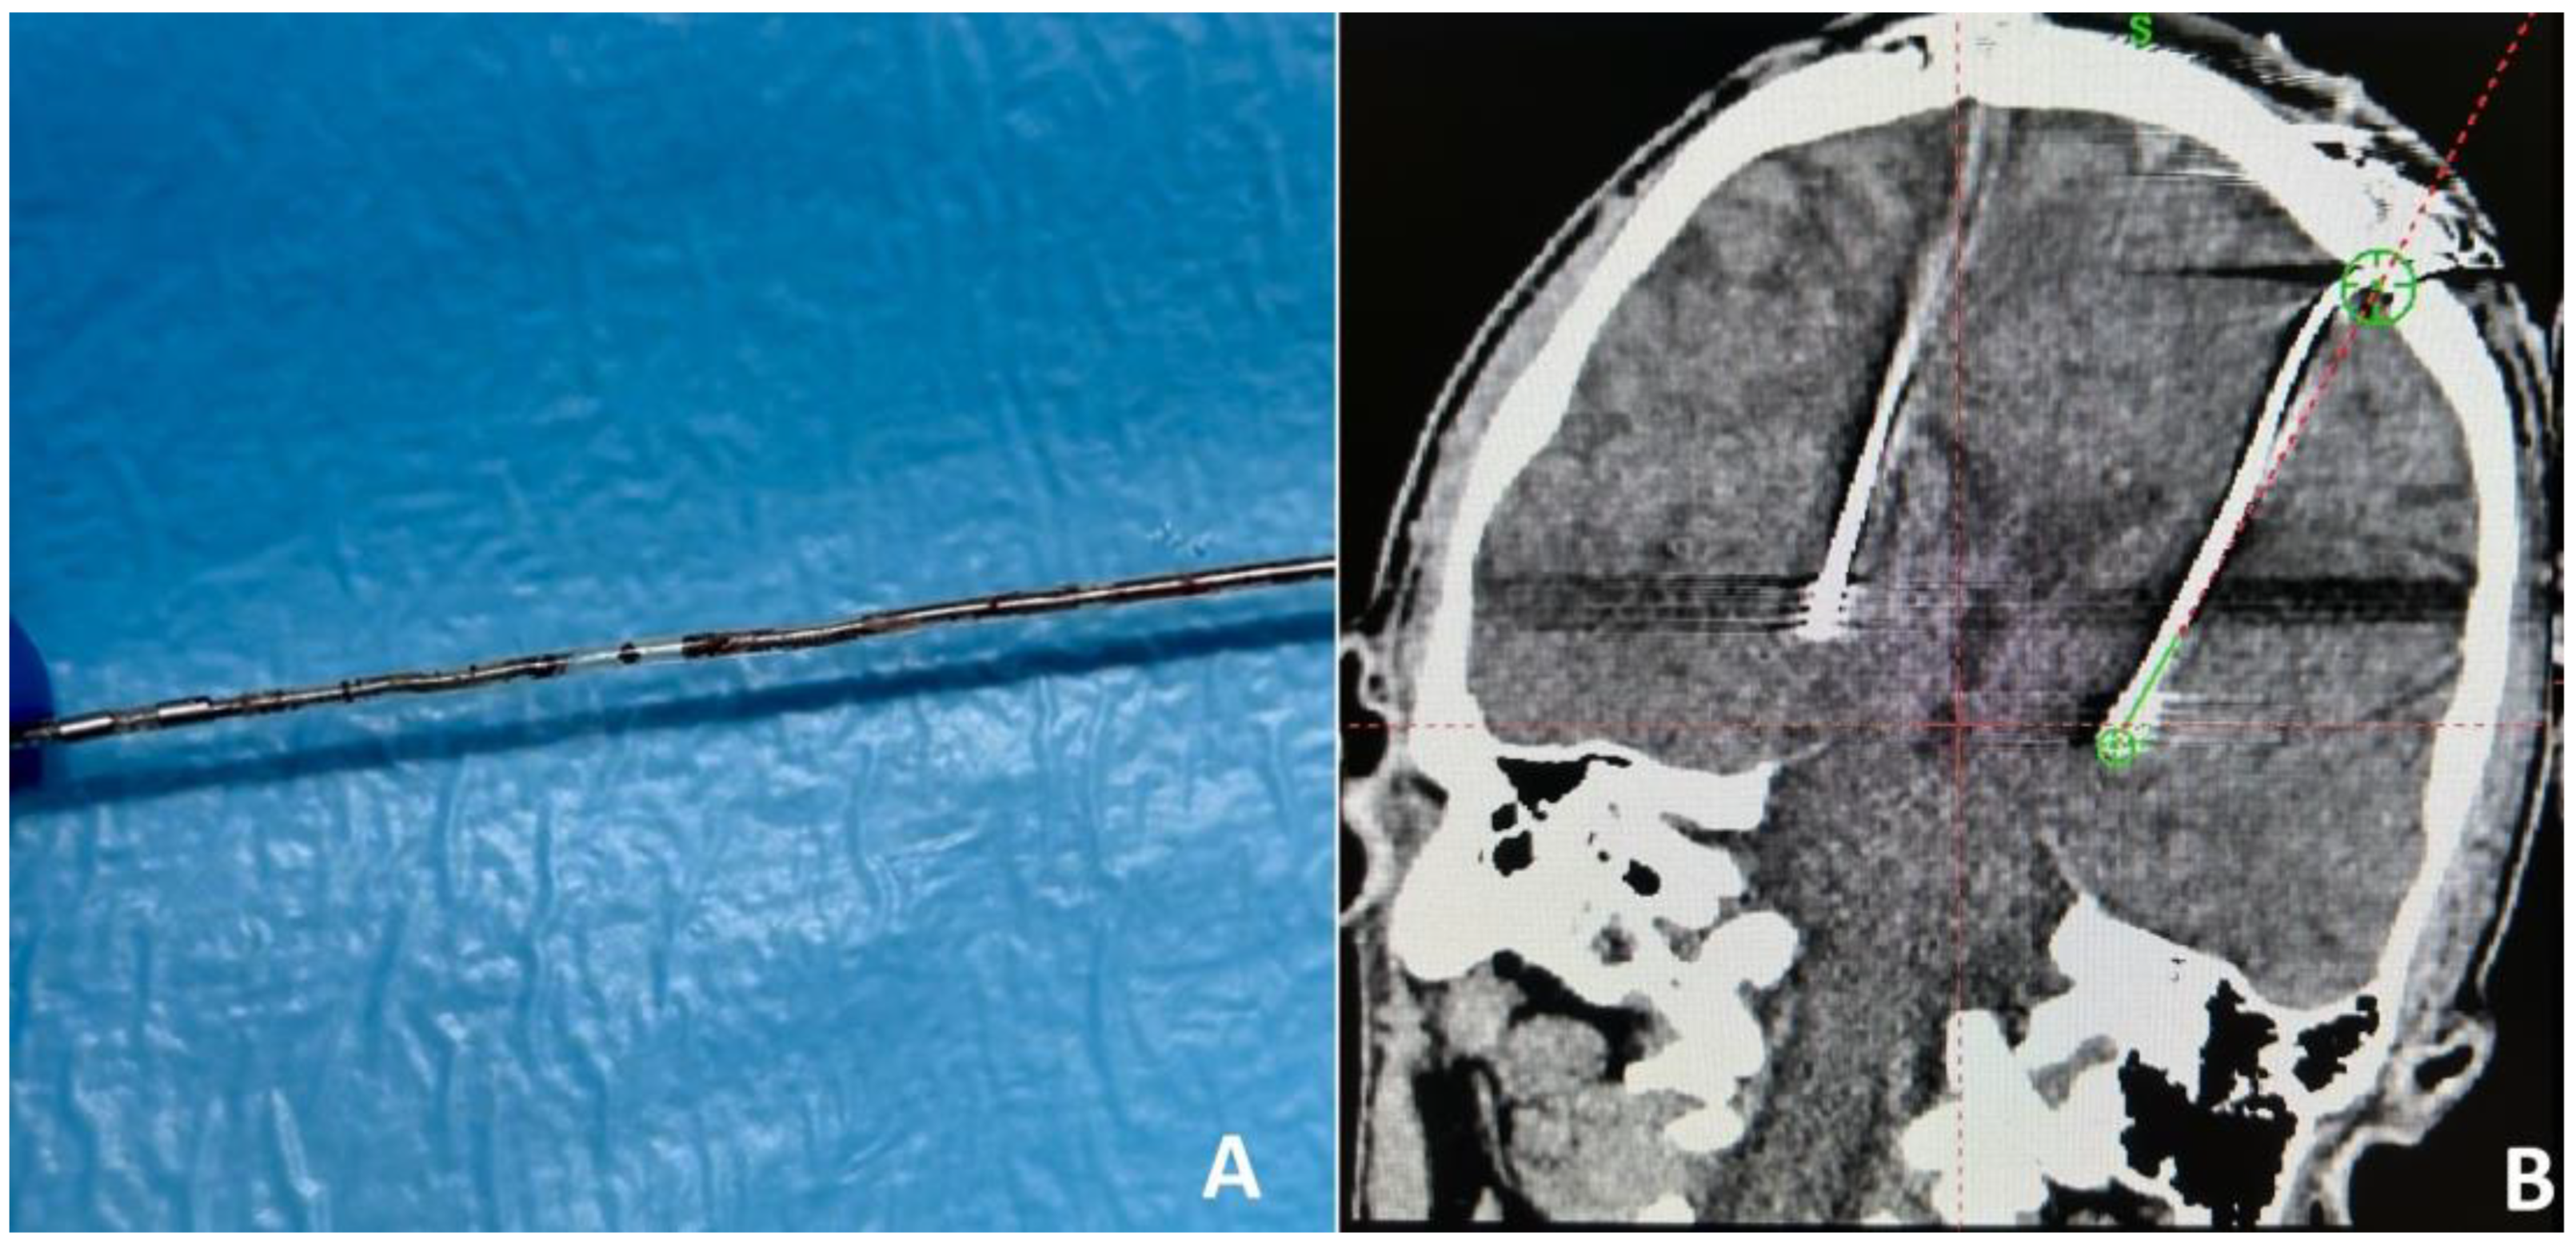

Illustrative case 3. Patient 9, a 32-year-old male with a 13-year history of the condition, had previously experienced significant symptomatic relief from bilateral GPi DBS and IPG (Activa PC) therapy for eight years. A routine replacement of the IPG was performed one year prior due to battery capacity exhaustion. The patient presented to the medical facility with acute involuntary muscle contractions in the neck, a symptom onset that followed physical exertion from pull-ups. This event prompted an urgent reassessment of the DBS system’s functionality. Initial impedance and current measurements indicated functional discrepancies across the electrodes: electrode 2 exhibited normal parameters, whereas electrodes 0, 1, and 3 showed elevated impedance levels (3946–4278) and reduced current (0.7 μA), suggesting the presence of three open circuits. Comprehensive cranial and chest radiographic examinations failed to reveal any structural anomalies within the hardware. An initial decision to revise the extension wires was made based on the diagnostic findings. However, this intervention did not yield an improvement in the patient’s symptoms. Further impedance assessments revealed persistently high levels across electrodes 0–3. Subsequent surgical exploration revealed a lead fracture at the junction between the intracranial electrode and its extension (Figure 3A), which was determined to be the underlying cause of the system’s malfunction. The patient underwent a successful stereotactic reimplantation of the left intracranial electrode and extension. Post-operative computed tomography (CT) imaging (Figure 3B) confirmed the precise placement of the newly implanted electrode within the targeted GPi region. The post-surgical period was marked by a notable improvement in the patient’s symptoms, aligning with the normalization of impedance levels across the evaluated electrodes.

Figure 3. Intracranial extension wire fracture (A). Post-operative frontal CT after intracranial electrode replacement (B).